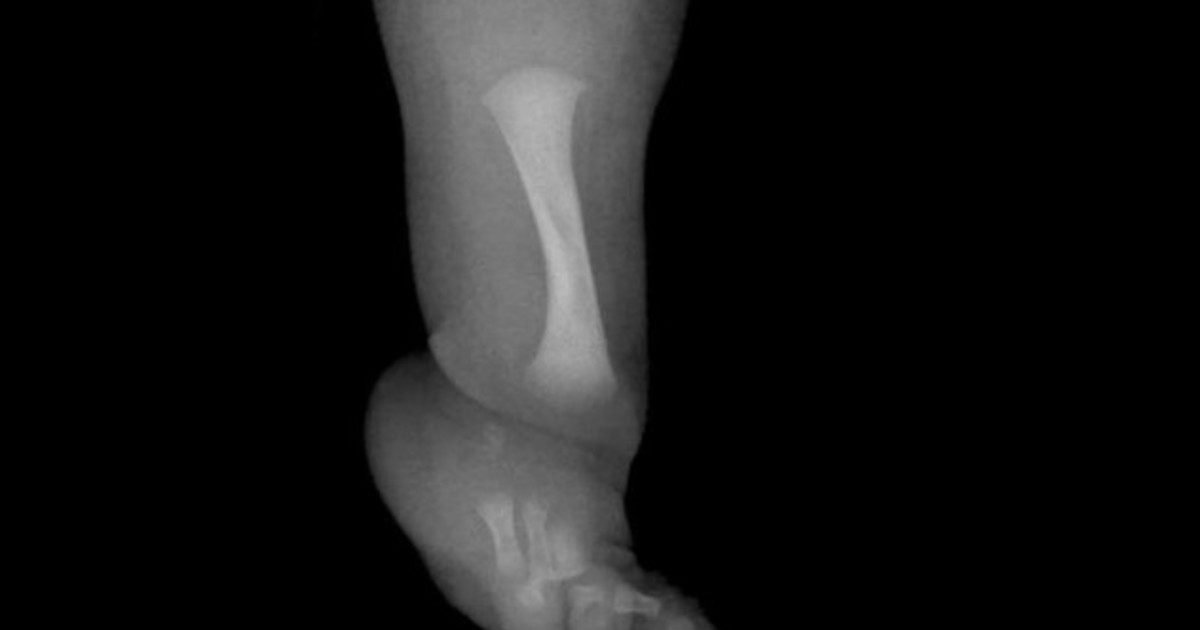

Un niño de nueve años se ha sometido en el Reino Unido a una cirugía pionera para menores para tratar la hemimelia fibular, lo que permitirá el desarrollo del peroné y corregir también su estatura.

Esta operación de alargamiento del hueso, efectuada por expertos del Hospital Infantil Alder Hey de Liverpool (norte de Inglaterra), ofrece una nueva solución para curar esta malformación congénita rara.